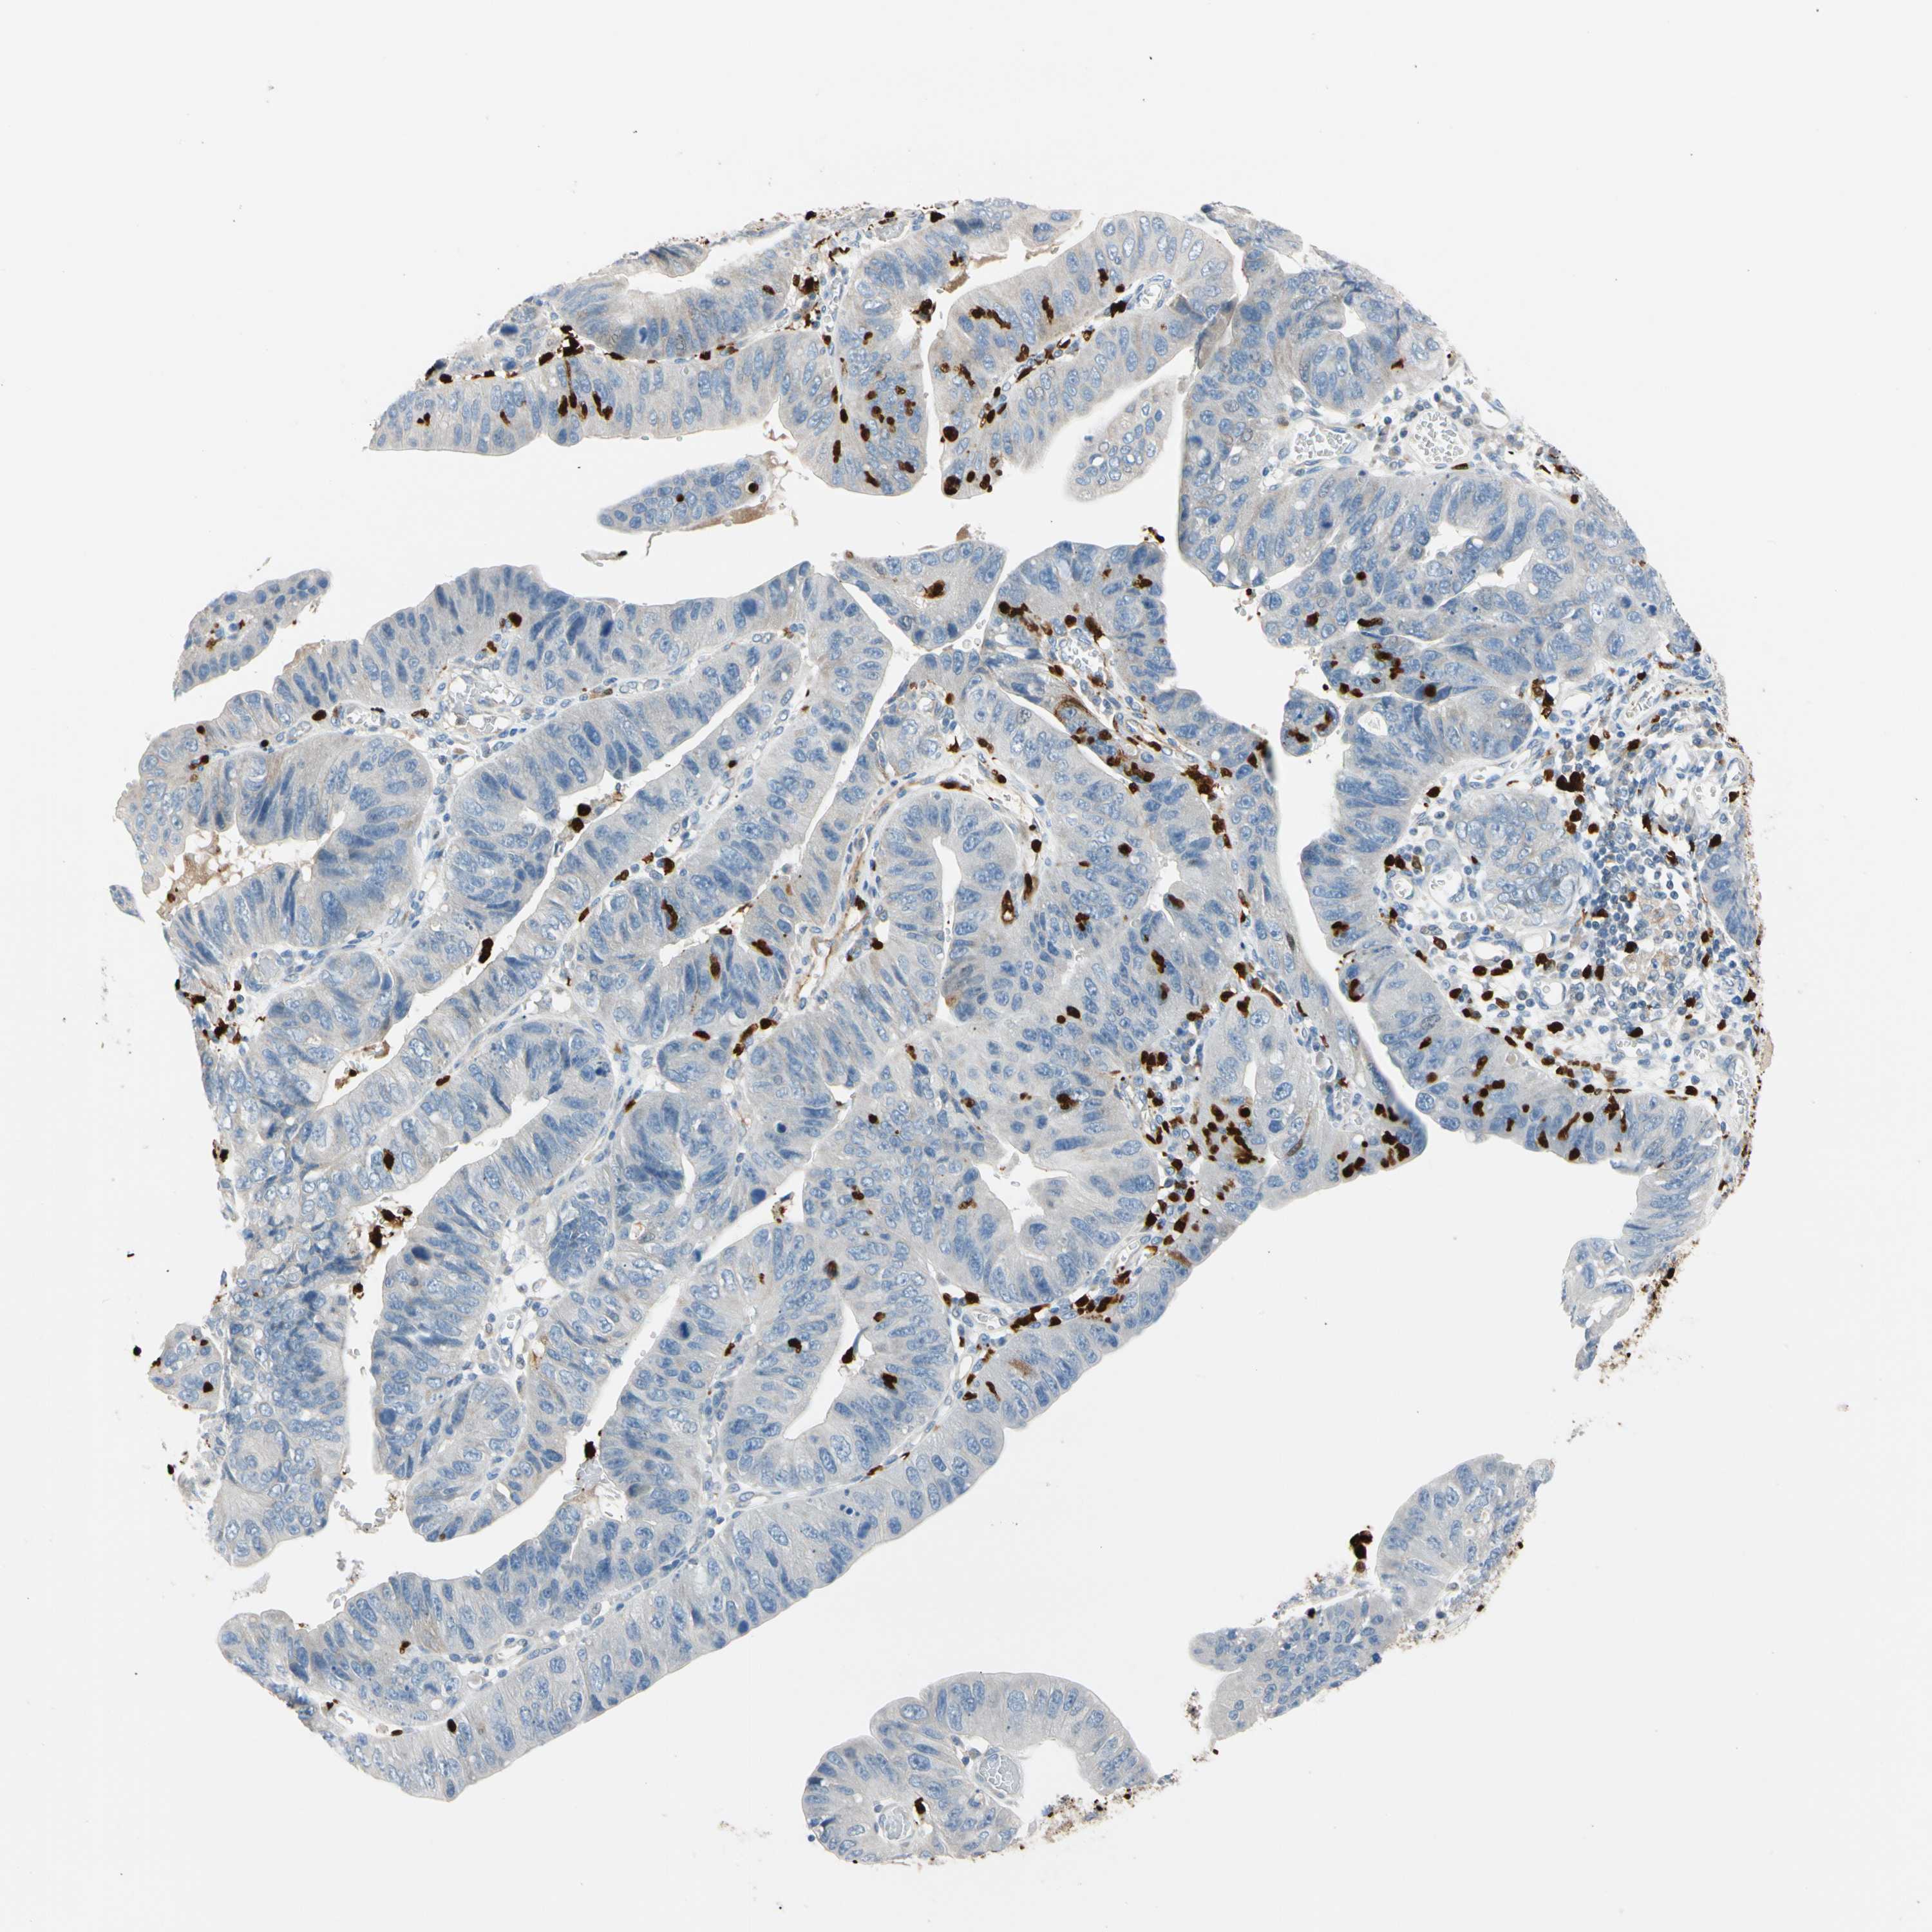

STOMACH CANCER - Protein expressioni

A mouse-over function shows sample information and annotation data. Click on an image to view it in a full screen mode. Samples can be filtered based on level of antibody staining by selecting one or several of the following categories: high, medium, low and not detected. The assay and annotation is described here.

Note that samples used for immunohistochemistry by the Human Protein Atlas do not correspond to samples in the TCGA dataset.

Antibody stainingi

Antibody staining in the annotated cell types in the current human tissue is reported as not detected, low, medium, or high, based on conventional immunohistochemistry profiling in selected tissues. This score is based on the combination of the staining intensity and fraction of stained cells.

Each image is clickable and will lead to virtual microscopy that enables deeper exploration of all samples and also displays staining intensity scores, fraction scores and subcellular localization as well as patient and tissue information for each sample.

Antibody HPA008052

Antibody CAB010277

Staining

High

Medium

Low

Not detected

Intensity

Strong

Moderate

Weak

Negative

Quantity

>75%

75%-25%

<25%

None

Location

Nuclear

Cytoplasmic/membranous

Cytoplasmic/membranous,nuclear

Adenocarcinoma, NOS

Adenocarcinoma, High grade